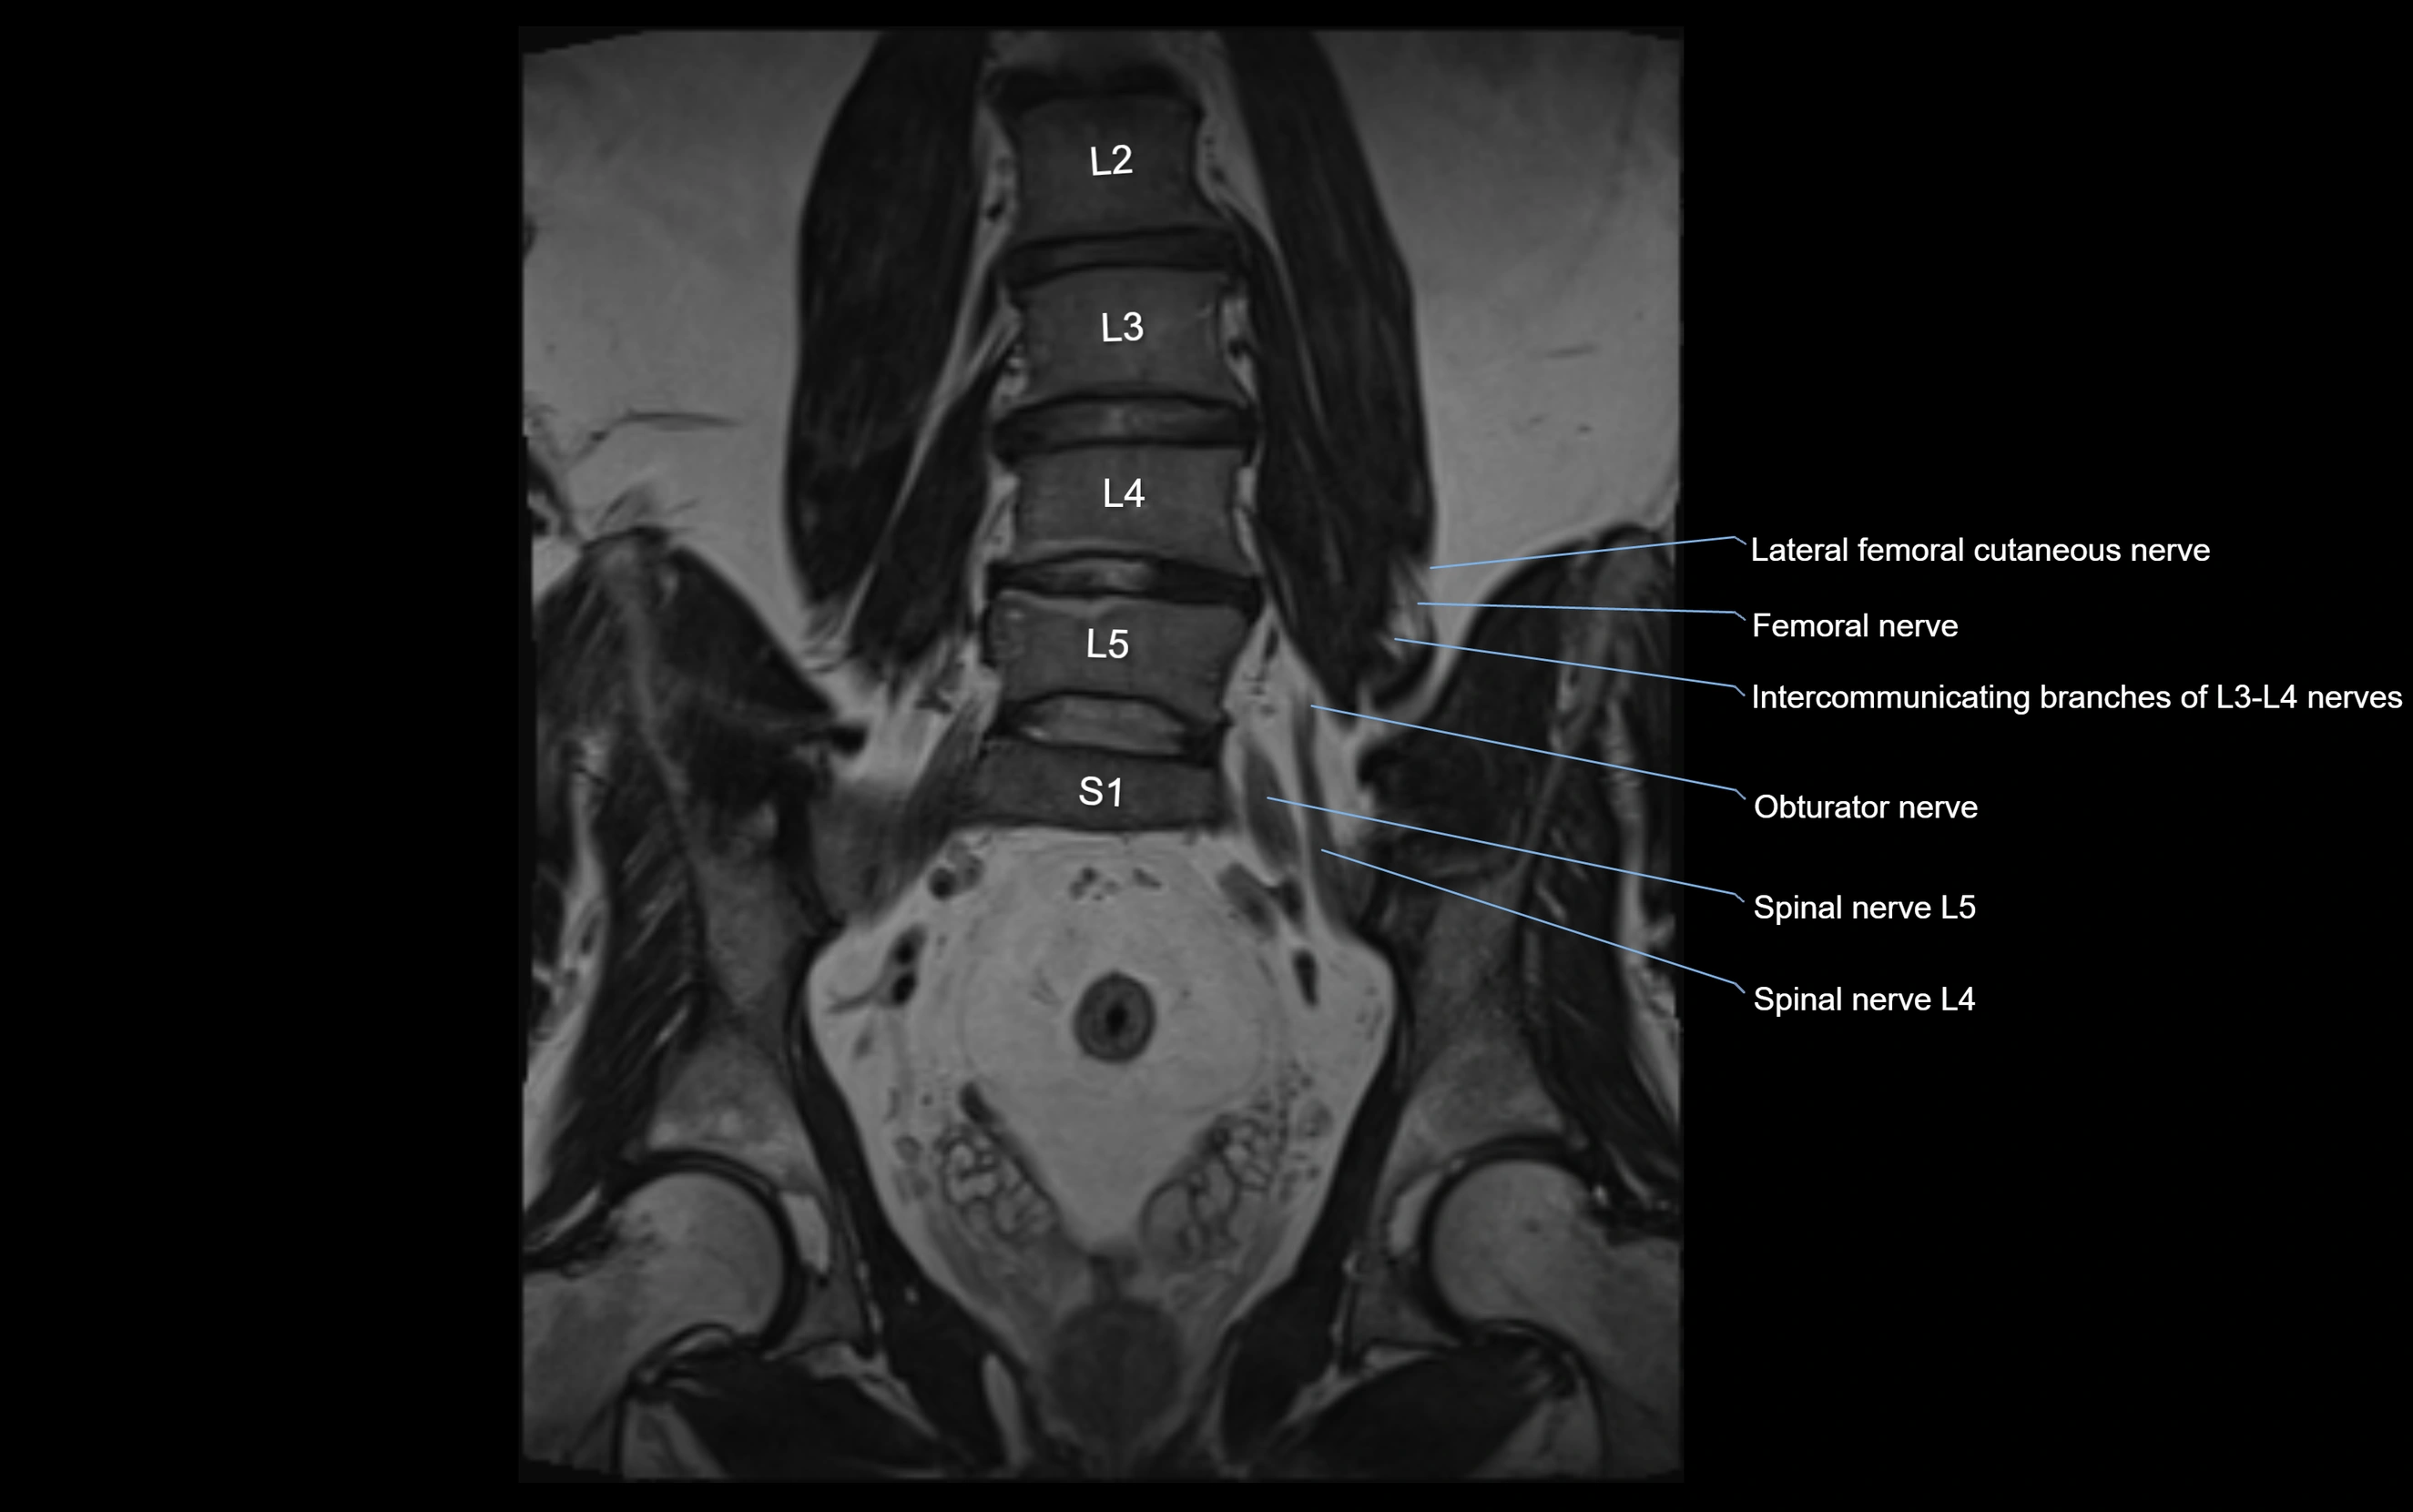

MRI image

image